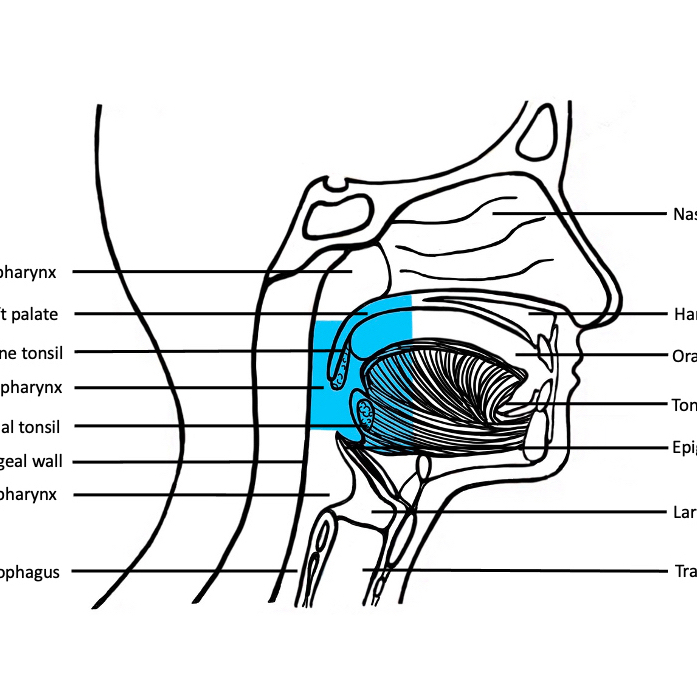

- Squamous cell carcinoma involving the oropharynx

- Oropharynx includes the soft palate, uvula, palatine tonsils, posterior third (base) of the tongue and posterior wall of the pharynx

Sites

- Oropharynx

- Most commonly soft palate